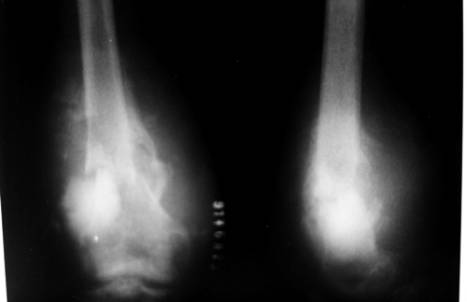

2)骨软骨瘤

①病理:软骨源性良性肿瘤,长骨干骺端的骨组织,软骨帽及滑囊,骨骺线闭合后,生长停止

②临床表现

a、多发生于青少年(10~20岁),多发性骨软骨瘤(骨软骨瘤病)有家族遗传史,有恶变倾向

b、干骺端无痛性骨性包块,或有压迫卡压症状。

c、X线:骨性突起,与正常骨相连。

③治疗:手术完整切除

pre-opg0534_1